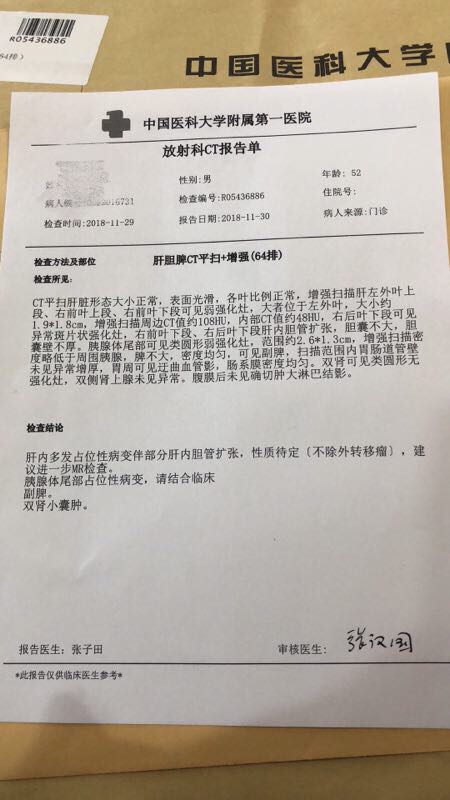

晨光1226 02019-03-13 患者家属我父亲52岁,在我过生日那天确诊胰腺癌晚期,并骨转移,肝转移,医院不建议化疗,无法手术,住院15天后医院不留,拿着片...